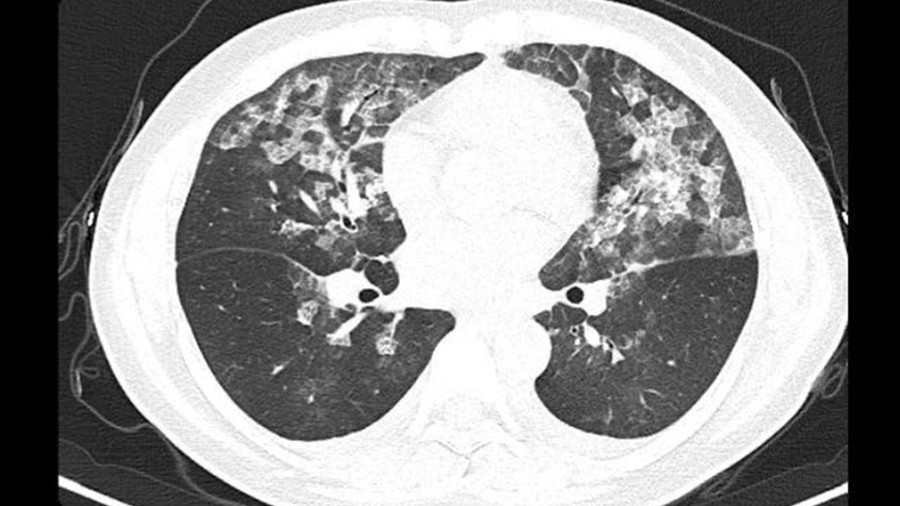

新型コロナウィルスへの警戒が続く中、病院はCTスキャンによる検査を行ったところ、患者の肺からすりガラス状の白い影が見つかった。それはまさに新型コロナ肺炎の特徴と一致するものだった。

CT写真の白い影は新型コロナ肺炎のそれとよく似ているものの、過去の接触歴、症状、血液検査いずれも新型コロナ肺炎のものとは合致せず、医師らを悩ませた。原因はまさかの「過剰コロナ対策」

このため医師らは、2人の女性に対し、新型コロナウイルスではなく、長時間にわたり高濃度の「84消毒液」を吸い込んだことによる“アレルギー性肺胞炎”との診断を下した。アレルギー性肺胞炎とは

2~3日後、改めて検査したところ、肺の影は基本的に消えていた。治療に当たった医師は「もし新型コロナ肺炎の治療基準に従って治療していたら、さらに病状が悪化していた可能性がある。」と振り返る。